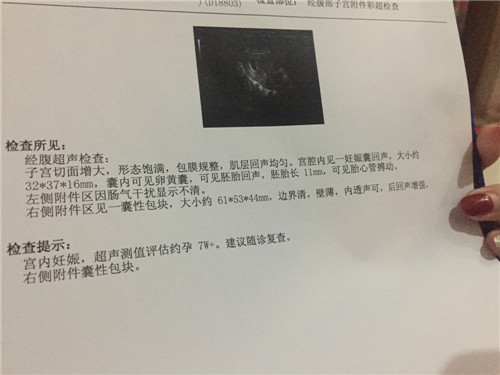

怀孕9周可以香港验血吗?亲身经历告诉你真相

怀孕9周可以香港验血吗?亲身经历告诉你真相每一个女性在得治自己怀孕以后想必心情都是无比激动兴奋的,每天都在期待憧憬着自己宝宝

大家如果只要看过关于香港验血验男女的条件检测技术,都是知道香港验血测性别是有几个条件的,不然达不到相应的准确率,其中一项就是在